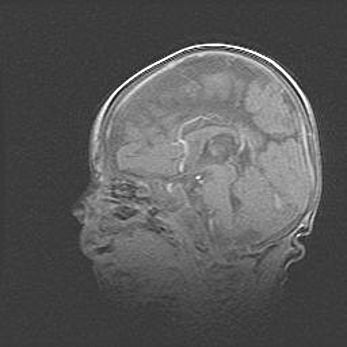

Множественные кисты обоих полушарий головного мозга, наибольшая из них в правой затылочной области. Ассиметричная атрофическая гидроцефалия.

Возраст: 7 месяцев

Вес: 5660 г

Пол: мужской

Окружность головы: 41,5 см

Срок гестации: 28-29 недель

Кисты головного мозга развиваются в результате многоочаговых некрозов вещества мозга и возникают вследствие перенесенной перинатальной инфекции, менингитов, энцефалитов, асфиксии, родовой травмы, расстройств мозгового кровообращения различного генеза. Образованию кист в веществе головного мозга плодов и новорожденных способствуют такие факторы, как высокое содержание в нем воды, недостаточная (или отсутствие) миелинизация и слабая астроглиальная реакция на повреждение.

Кисты могут сочетаться с гидроцефалией и другими поражениями головного мозга.